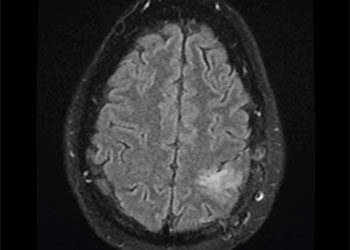

Brain:

Atypical Convexity Meningioma

Author: Jonathan L. Brisman M.D., F.A.C.S., Read More!